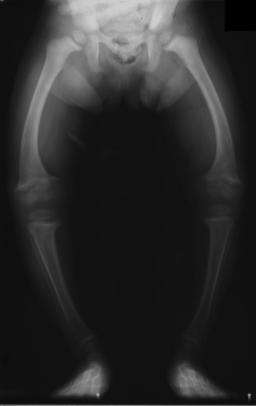

Primidone, along with phenytoin and phenobarbital, is one of the anticonvulsants most heavily associated with bone diseases such as osteoporosis, osteopenia (which can precede osteoporosis), osteomalacia and fractures.[39][40][41] The populations usually said to be most at risk are institutionalized people, postmenopausal women, older men, people taking more than one anticonvulsant, and children, who are also at risk of rickets.[39] However, it has been suggested that bone demineralization in most pronounced young people (25–44 years of age)[40] and one 1987 study of institutionalized people found that the rate of osteomalacia in the ones taking anticonvulsants—one out of nineteen individuals taking an anticonvulsant (vs. none among the thirty-seven people taking none) —was similar to that expected in elderly people. The authors speculated that this was due to improvements in diet, sun exposure and exercise in response to earlier findings, and/or that this was because it was sunnier in London than in the Northern European countries which had earlier reported this effect.[41] In any case, the use of more than one anticonvulsant has been associated with an increased prevalence of bone disease in institutionalized epilepsy patients versus institutionalized people who did not have epilepsy. Likewise, postmenopausal women taking anticonvulsants have a greater risk of fracture than their drug-naive counterparts.[39]

Anticonvulsants affect the bones in many ways. They cause hypophosphatemia, hypocalcemia, low Vitamin D levels, and increased parathyroid hormone. Anticonvulsants also contribute to the increased rate of fractures by causing somnolence, ataxia, and tremor which would cause gait disturbance, further increasing the risk of fractures on top of the increase due to seizures and the restrictions on activity placed on epileptic people.Increased fracture rate has also been reported for carbamazepine, valproate and clonazepam. The risk of fractures is higher for people taking enzyme-inducing anticonvulsants than for people taking non-enzyme-inducing anticonvulsants.[40] In addition to all of the above, primidone can cause arthralgia.[33]